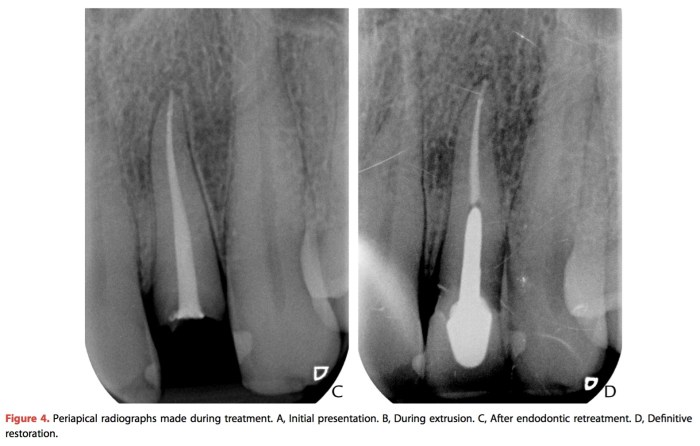

使用鄰牙來做orthodontic extrusion的case report—Re(2016) 2016 年 11 月 07 日2016 年 11 月 09 日 yehhsinchi 診斷、固定式假牙診斷、固定式假牙 jpd-2016-vol-116-p-464-466 在前牙有時候可能會遇到這樣的情形,就是之前做的單顆假牙斷了然後subgingiva,但是牙根還不錯,想要做局部矯正拉出來,這個case report是利用兩側的鄰牙去拉,在某些情形下可是使用看看。 分享此文: 分享到 X(在新視窗中開啟) X 分享到 Facebook(在新視窗中開啟) Facebook 喜歡 正在載入...